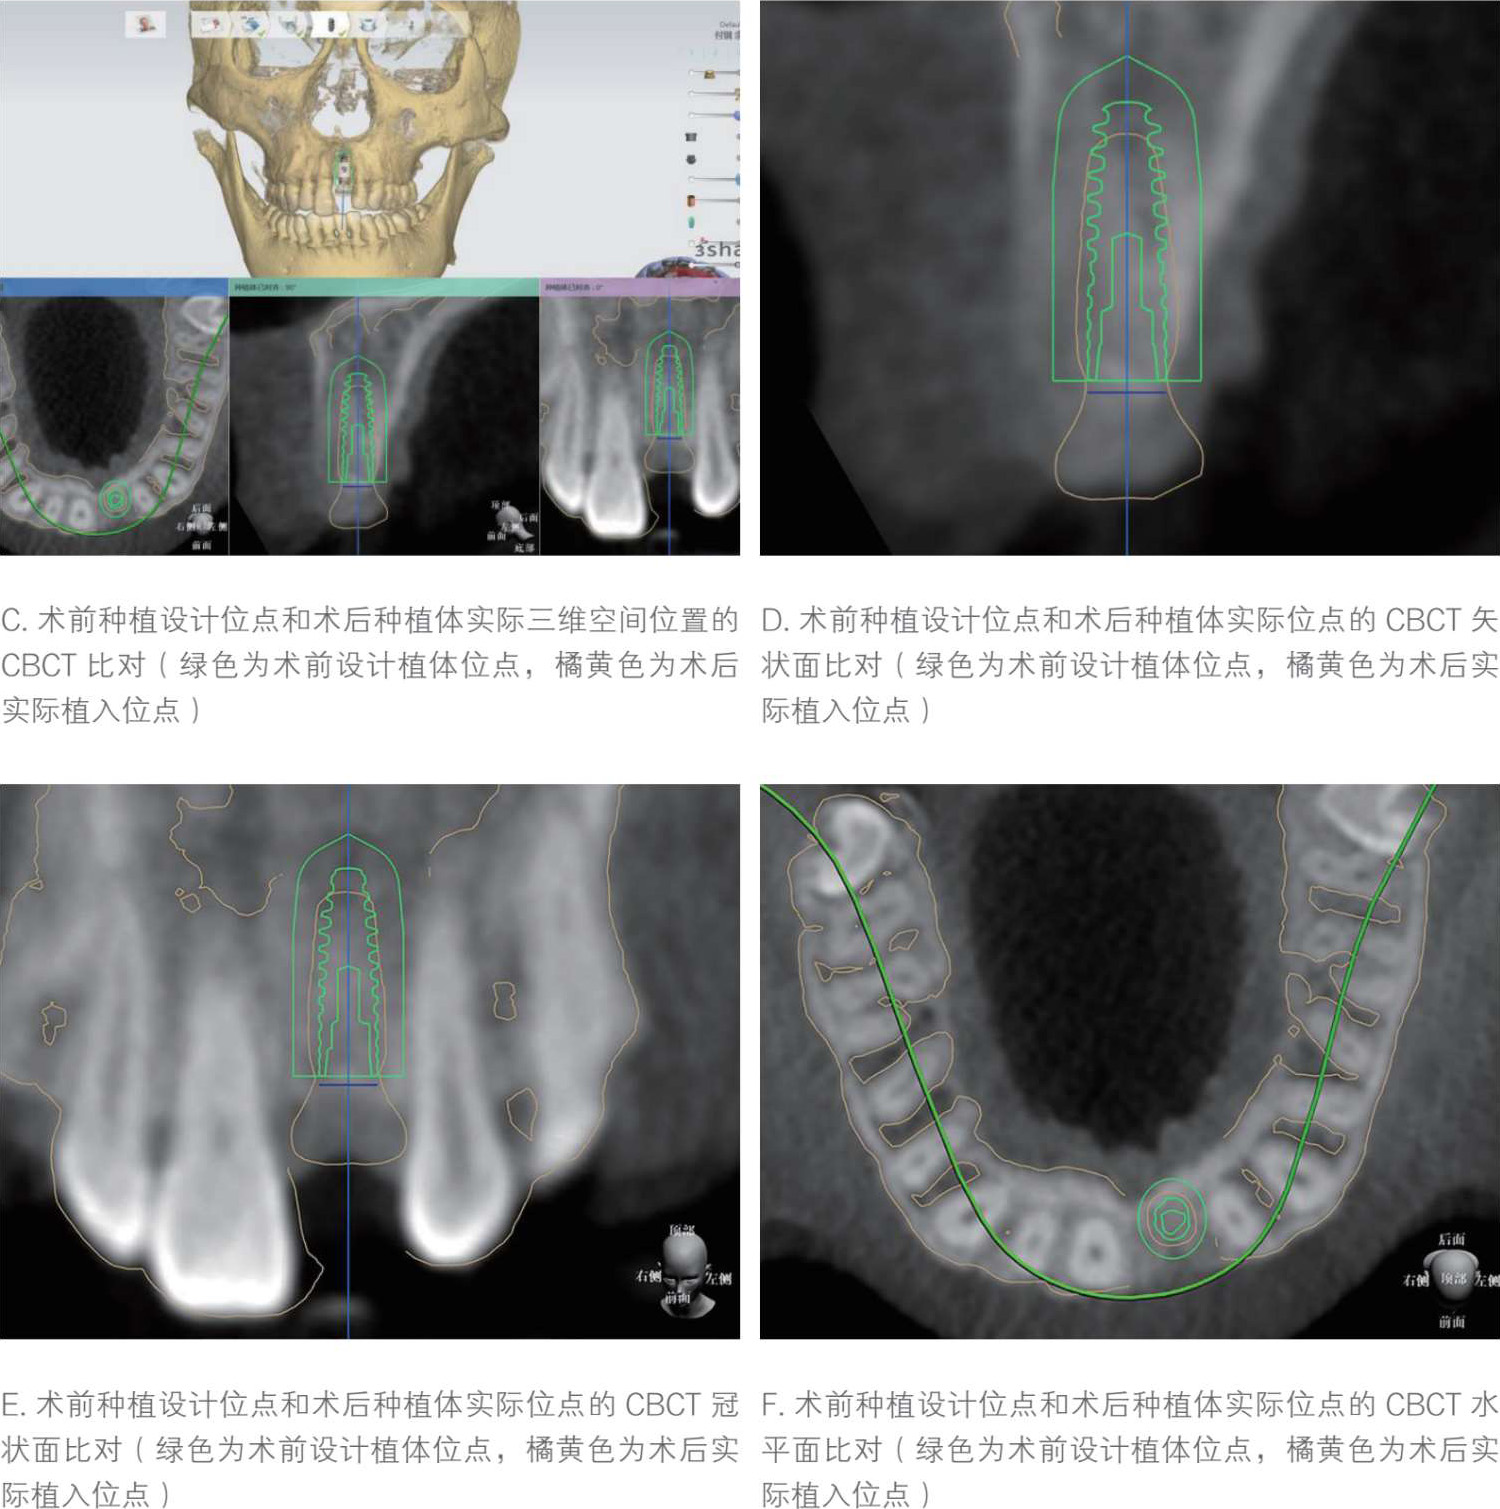

在种植手术及修复完成后,通过对比修复体的虚拟设计和实际效果(图 1-1-6 A,图 1-1-6 B),以及种植体的虚拟设计与实际位置(图 1-1-6 C—图 1-1-6 F),实现虚拟设计与实际效果的对比验证,并分析出现偏差的原因,从而获得临床技术步骤的效果验证与反馈。

图1-1-6 最终修复效果和位点的设计与完成比对